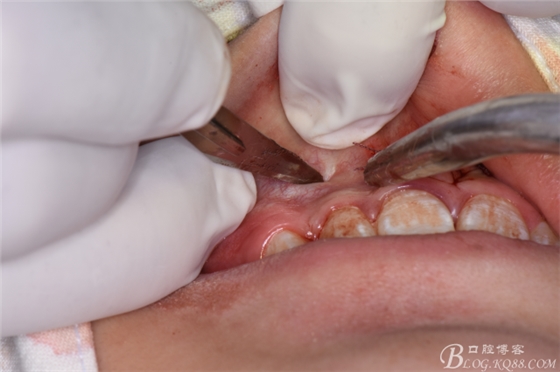

圖21.一定要切透粘骨膜。

圖22.翻瓣、暴露骨面